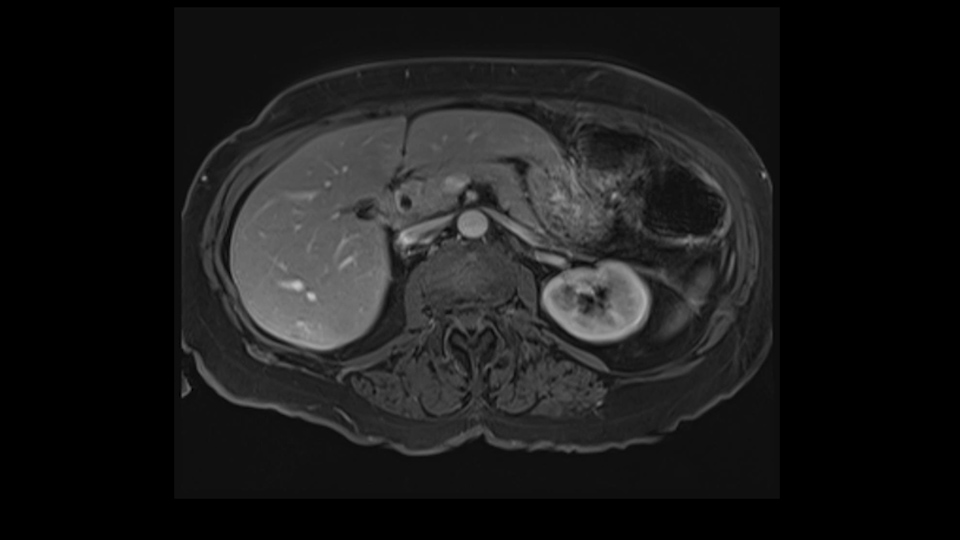

She underwent neo-adjuvant chemotherapy and then had a series of additional investigations and the one that I’m focusing on in more finer detail is an MRI with Primovist and I’ve had the benefit of looking at the report. The main issues are in Segments 5,6, and 7. Three small metastases that remain and the radiologist also comments on the lack of biliary dilatation which was present before; implying that the intrabiliary metastasis somewhere at the origin of the Segment 7 duct, has regressed or been adequately well treated with chemotherapy. That’s probably where the difficult decision making comes in the OR. So from an oncologic point of view, I would plan for a right hepatic lobectomy. The rationale would be that this would include the more peripheral Segment 5, 6, 7 metastases that are obvious but also would take care of the presumed Segment 7 intrabiliary metastasis that does not actually visualize on any of the scans but is assumed to be there with evidence of the duct dilatation which then resolved. One could argue whether we should preserve liver and ignore that duct dilatation that was there before but I think my own preference would be to resect the right lobe and that would certainly include any residual disease in that Segment 7 bile duct and moreover, coming back to do a completion right hepatic lobectomy would be difficult particularly around the porta where this metastasis is presumably still there and even if its quite small.

Finally the bile duct is divided in the liver. I can actually see this patient’s bile duct. It’s a bit dilated and she had cholecystectomy. I think we would divide the bile duct in the liver. It’s hard to anticipate from a CT scan what you’re going to see because you can’t actually see the bile duct very well on the average CT.

![[Sg7 branch]](jpg/preop_sg_moment6.jpg)

So overall I would plan to do a right hepatic lobectomy. The slowing down moments are the usual ones: carefully mobilizing the right lobe, not injuring the main hepatic veins or the vena cava, the right portal vein split, the length of the right portal vein. The rest looks very routine. The oncologic issue I’ve already decided I’m going to do a right lobe with the assumption that there is an intrabiliary metastasis somewhere near the origin of the right- the Segment 7 duct and probably close to the bifurcation of the main right bile duct so the best way to get a margin is to actually divide the right bile duct close to its origin the way you would normally do a right hepatic lobectomy.

Coming up a little bit higher. There’s a little bit of biliary dilatation as well. On the right side of the liver. Which may be nothing but it may be an indicator or harbinger of nodal disease in the hepatoduodenal ligament so something to be aware of. If the enzymatic liver function tests are normal and there’s no evidence of a stone in the common bile duct on cross sectional imaging you wouldn’t need to do anything about it but just to be aware of that.![[RHV]](jpg/preop_as_p4.jpg)

In this case, with this specific case, one of the things that I was a little concerned about was that biliary dilatation because biliary dilatation isn’t normally part of the kind of landscape of metastatic colorectal cancer unless there are lymph nodes enlarged in the hepatoduodenal ligament. So I would, in this case, I would specifically look at the hepatoduodenal ligament to see whether she’s got enlarged lymph nodes. If they’re enlarged and they spread all the way down, if there’s a chain of enlarged lymph nodes running behind the back of pancreas, that can be seen as contraindication to liver resection because it means that there’s regional metastatic disease which isn’t going to be resected by a liver resection. So that biliary dilatation is a little bit of a source for concern. The other thing is that there is a way of predicting how patients will do from liver resection. Quite often referred to as the Fong Score. Here, there are more than one metastases, 3 or 4 metastases. So that’s the one point that’s beginning to indicate that maybe the prognosis is a little worrying but it wouldn’t stop you doing a resection. A resection would be an appropriate thing to do here.